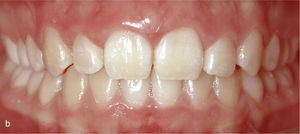

La situación intraoral después de finalizar el tratamiento (figs. 16a a 16e) muestra, como lo hacen los modelos montados en relación céntrica (figs. 17a a 17e), una clase I de Angle con relación intermaxilar anterior fisiológica y una guía canina asegurada. En la radiografía panorámica final no se observan signos patológicos; se indicó la extracción de los terceros molares inferiores (fig. 18). El paciente utilizó férulas de Imprelon durante la noche como sistema de retención (Scheu-Dental, Iserlohn).